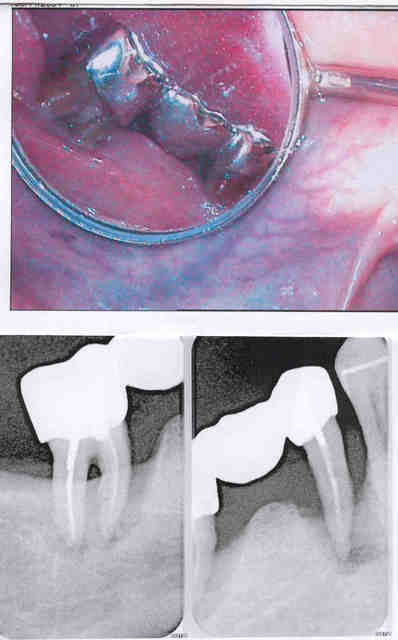

pis voila!

Après vwbedb - Eugenol

Itou m0p00m - Eugenol

que nenni mon Zorbec, je joue plutot la transparence en direct live car c'est un cas que j'avais soumis en son temps dans la rubrique paro

tu m'avais dit:" je n'ai pas eu de cours d'acrobatie "!!...

j'ai essayé ( retraitement endo etc...) ...ca a pas marché...

mais j'ai pas salopé l'os pour les éventuels implanto